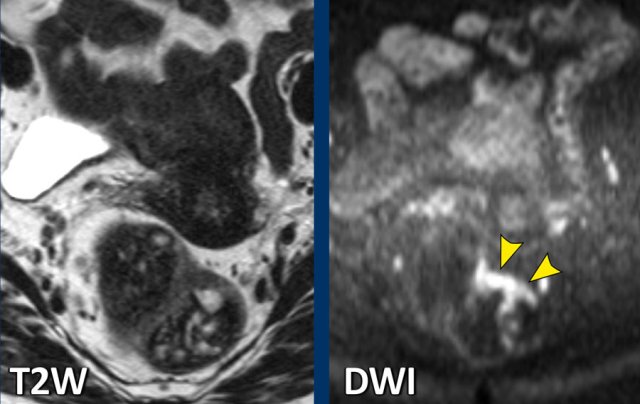

Images

The

images show the primary staging and restaging T2-weighted images after

chemoradiotherapy with predominant fibrosis with minor signal heterogeneity

(TRG 3).

The corresponding restaging DWI shows a focal area of high

signal at the inner margin of the fibrosis with corresponding low signal on the

ADC map, indicating restricted diffusion.

This

was confirmed to be a small tumor remnant (ypT2) at histopathology.